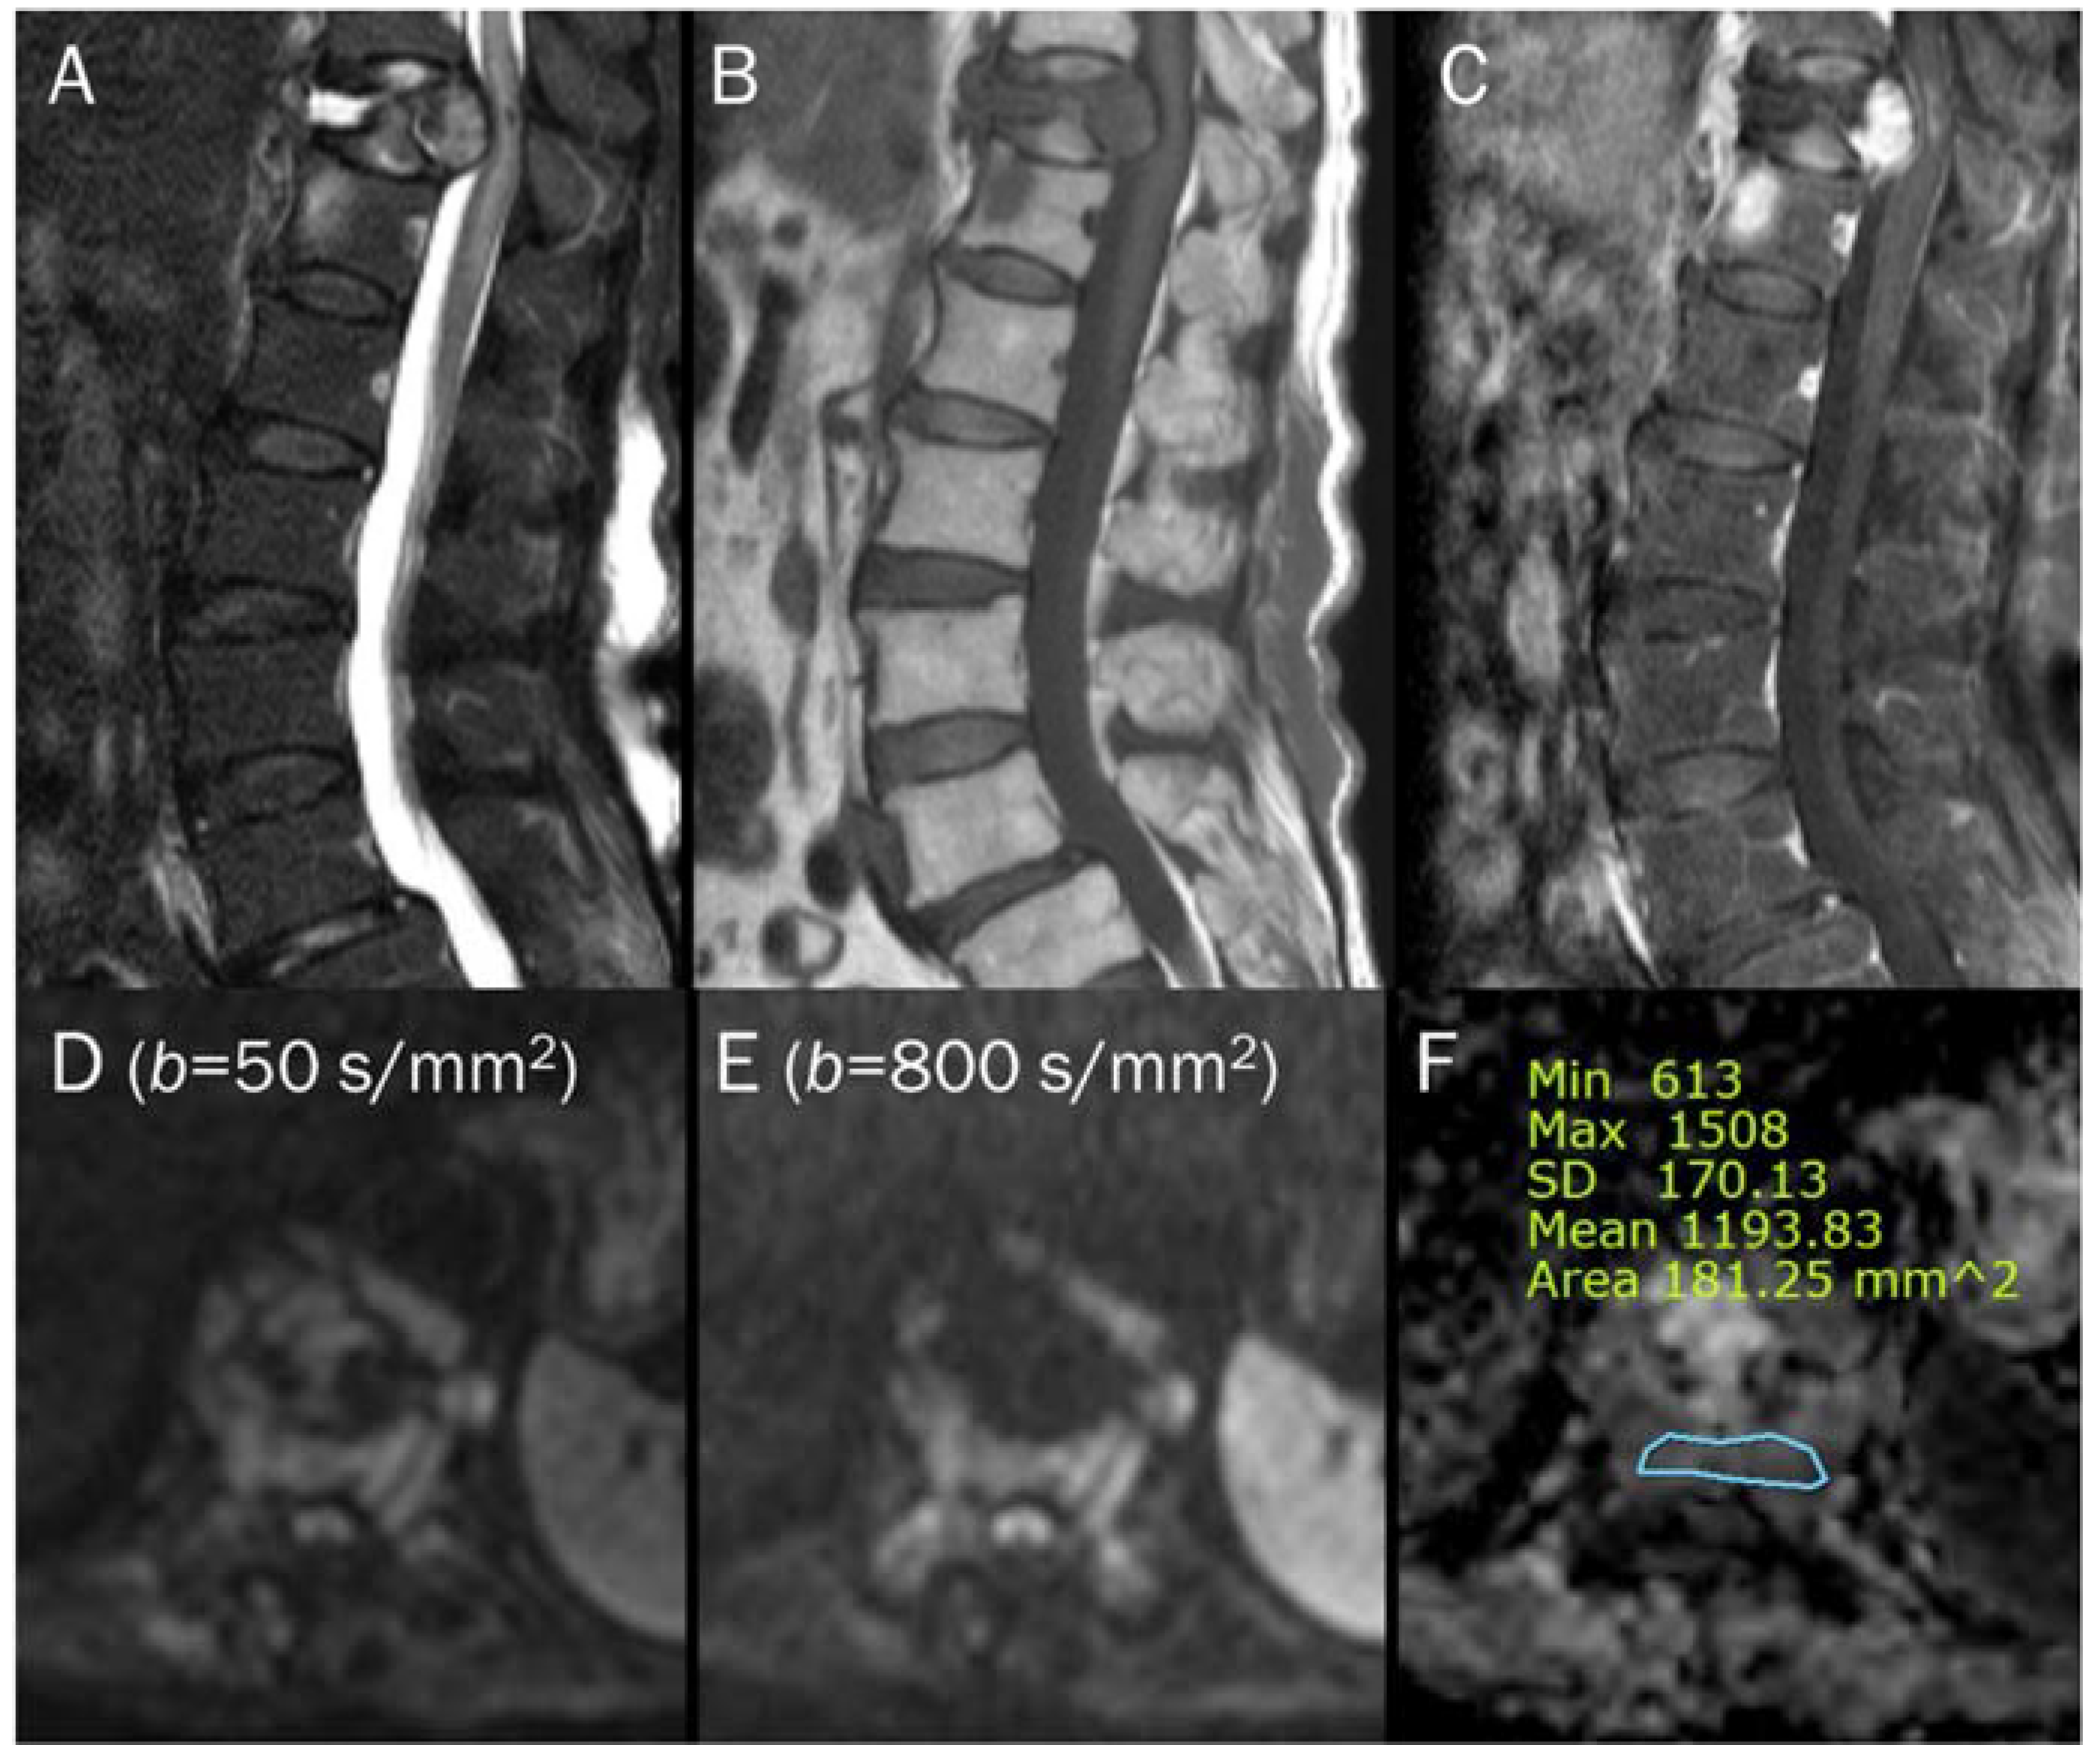

7.4. Vertebral Endplate Changes

- Modic, M.T.; Steinberg, P.M.; Ross, J.S.; Masaryk, T.J.; Carter, J.R. Degenerative disk disease: Assessment of changes in vertebral body marrow with MR imaging. Radiology 1988, 166, 193–199. [Google Scholar] [CrossRef]

- Braithwaite, I.; White, J.; Saifuddin, A.; Renton, P.; Taylor, B.A. Vertebral end-plate (Modic) changes on lumbar spine MRI: Correlation with pain reproduction at lumbar discography. Eur. Spine J. Off. Publ. Eur. Spine Soc. Eur. Spinal Deform. Soc. Eur. Sect. Cerv. Spine Res. Soc. 1998, 7, 363–368. [Google Scholar] [CrossRef]

- Oztekin, O.; Calli, C.; Kitis, O.; Adibelli, Z.H.; Eren, C.S.; Apaydin, M.; Zileli, M.; Yurtseven, T. Reliability of diffusion weighted MR imaging in differentiating degenerative and infectious end plate changes. Radiol. Oncol. 2010, 44, 97–102. [Google Scholar] [CrossRef]

- Patel, K.B.; Poplawski, M.M.; Pawha, P.S.; Naidich, T.P.; Tanenbaum, L.N. Diffusion-weighted MRI “claw sign” improves differentiation of infectious from degenerative modic type 1 signal changes of the spine. AJNR Am. J. Neuroradiol. 2014, 35, 1647–1652. [Google Scholar] [CrossRef]

| Modic type 1 vertebral endplate change | T2 black-out | Lipid laden cells |